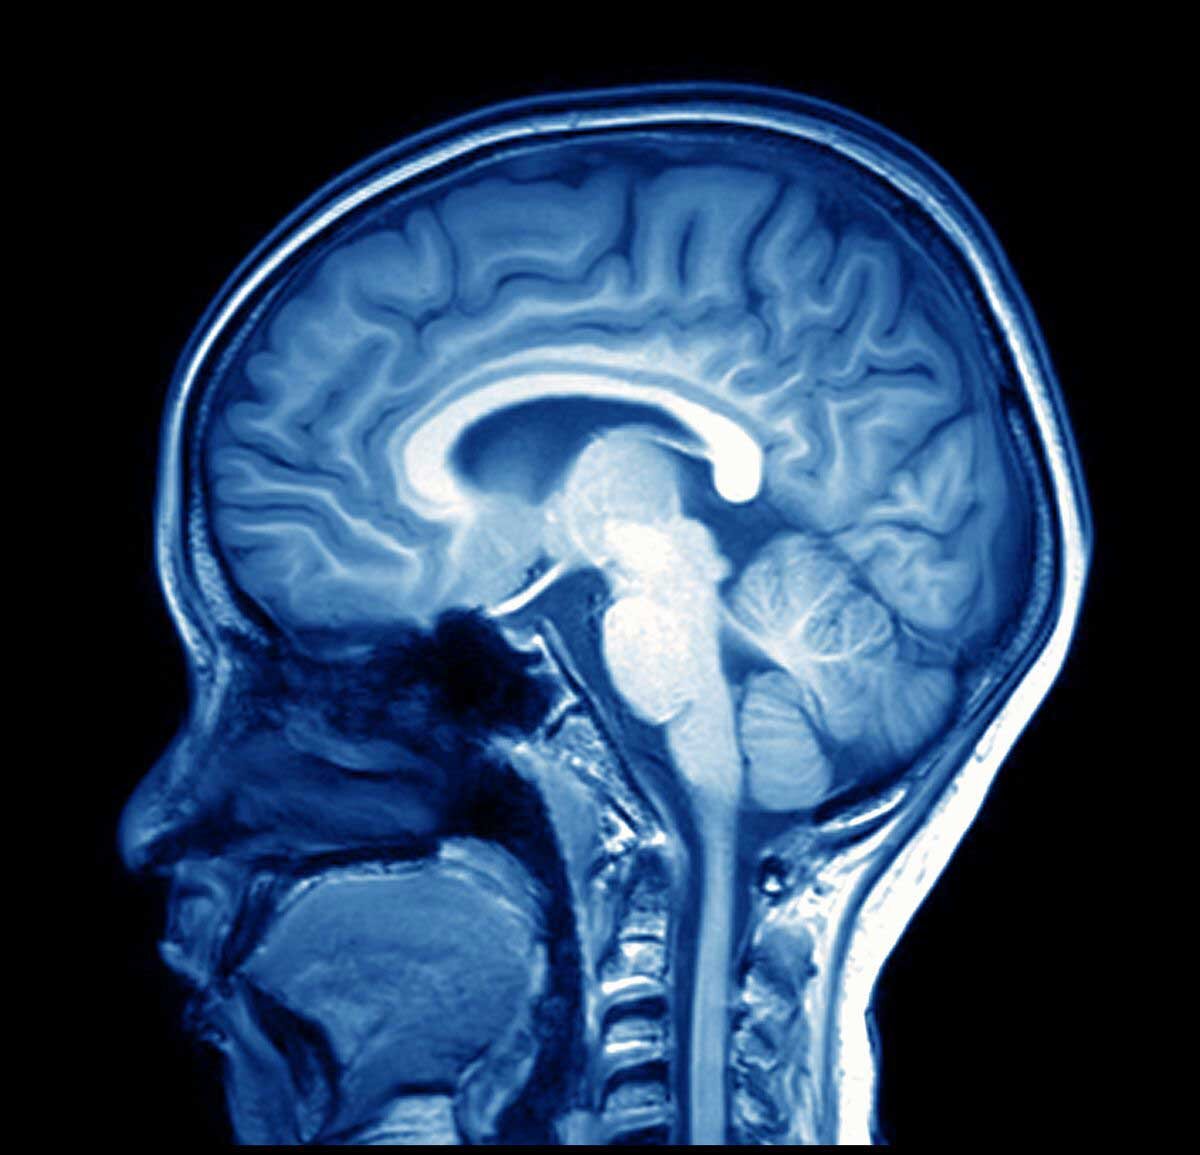

Исследовательские Группы Получают Разные Результаты На Основе Одних И Тех Же Данных Сканирования Мозга

Нейровизуализация, в частности функциональная магнитно-резонансная томография (фМРТ), которая производит картины паттернов кровотока в головном мозге, которые, как полагают, связаны с нейронной активностью, в прошлом подвергалась критике за такие проблемы, как плохой дизайн исследования и статистические методы, а также уточнение гипотез после того, как результаты известны (шулерство), говорит невролог Ален Дагер из Университета Макгилла, который не участвовал в исследовании. Особенно запоминающейся критикой этого метода была статья, демонстрирующая, что без необходимых статистических поправок он может идентифицировать видимую мозговую активность у мертвой рыбы.

Исследование, проведенное Шонбергом совместно с психологом Расселом Полдраком из Стэнфордского университета и статистиком по нейровизуализации Томасом Николсом из Оксфордского университета, привлекло независимые группы исследователей по всему миру для анализа и интерпретации одних и тех же необработанных данных нейровизуализации—сканирования мозга 108 здоровых взрослых, сделанных в то время, когда испытуемые находились в состоянии покоя и выполняли простую задачу принятия решения о том, стоит ли рисковать суммой денег.